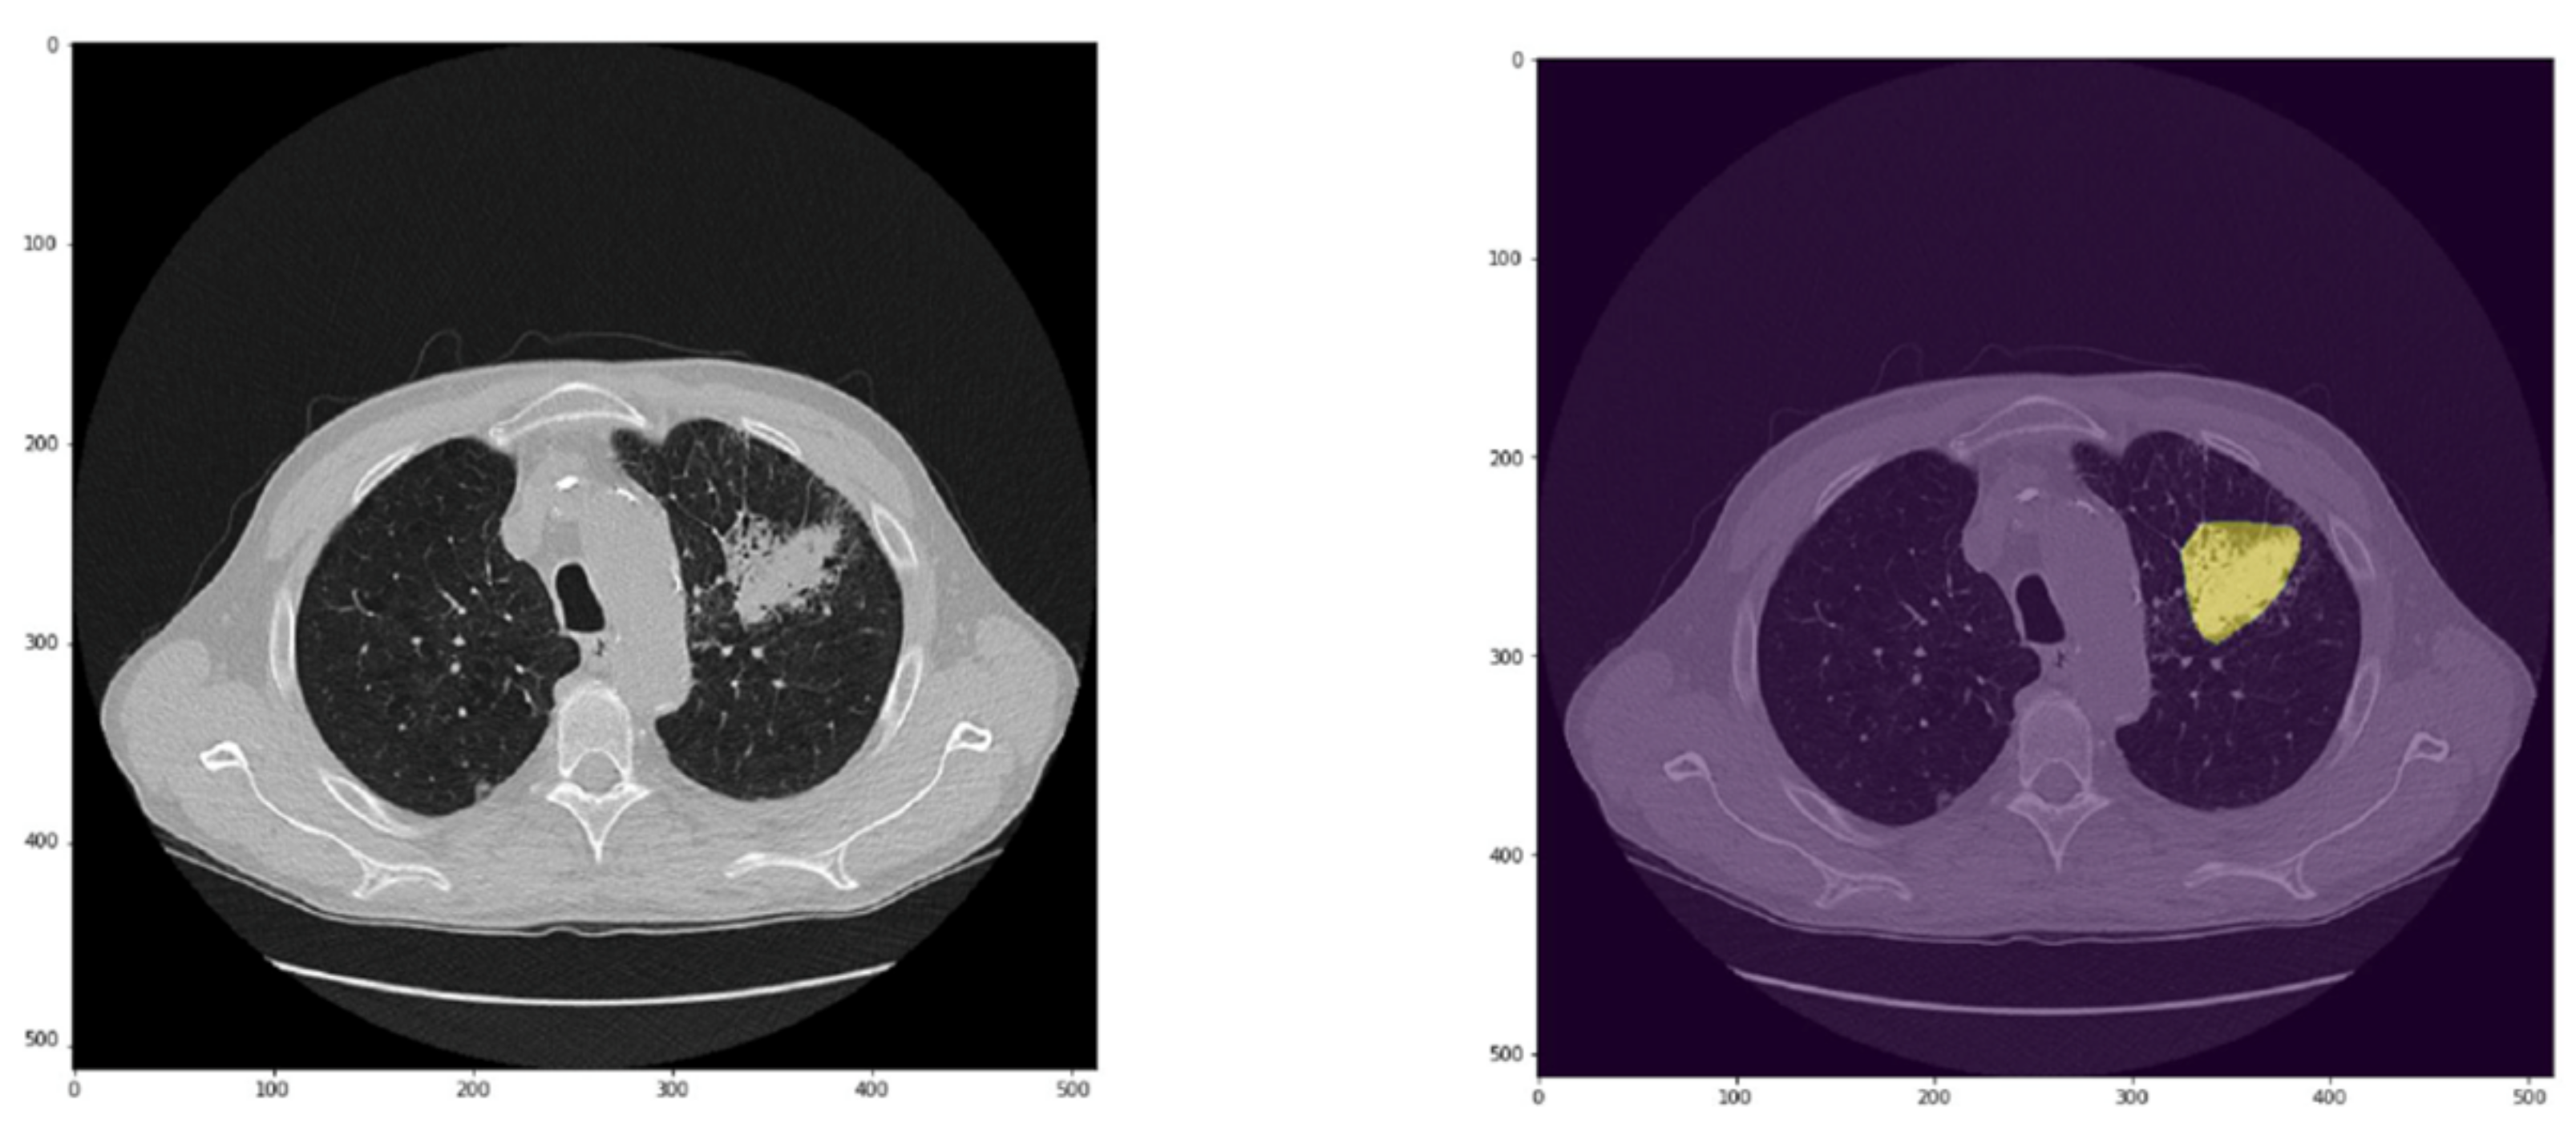

Figure 5. Example of a nodule close to pleura in the right lung correctly predicted by the CADe and of a small nodule, near to the previous one, missed by the CADe. Left panel: axial CT slice with prediction (yellow) and/or mask (pink); right panel: original CT image.

CADe correctly identified 96/123 nodules (78%) and missed 27/123 nodules. Specifically, 90/104 and 6/19 nodules of the ICH_s1 and ICH_s2 datasets, respectively, were detected correctly. Failures were relayed mainly on ground glass opacity (n = 6) and very small or very large nodules close to vessels, pleura (Figure 5), and/or mediastinum (n = 6, n = 9, and n = 4, respectively).